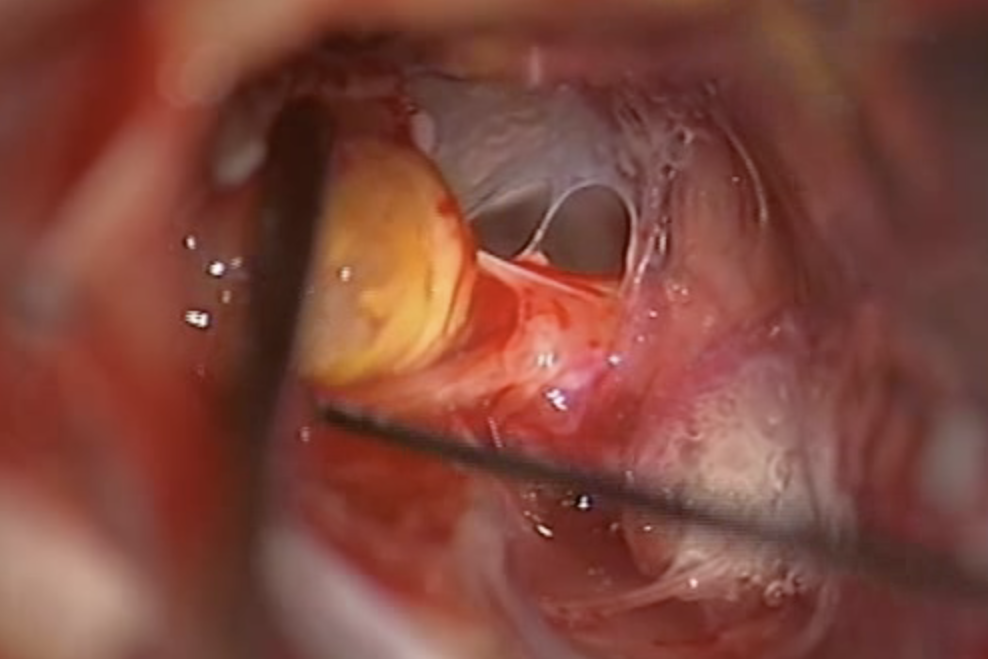

(Vienna, 15 June 2021) Vestibular schwannoma (acoustic neuroma) is a rare benign tumour of a vestibular portion of the vestibulo-cochlear nerve that is diagnosed from the symptoms of hearing loss, vertigo and tinnitus. Smaller tumours are usually treated by radiotherapy but larger ones require surgical removal. A clinical study led by MedUni Vienna has now shown that early surgical removal of a vestibular schwannoma preserves hearing in up to 83% of cases. The results have recently been published in the journal "Otolaryngology–Head and Neck Surgery".

Together with colleagues from the University of Erlangen, a MedUni Vienna team led by Karl Rössler, Head of the Department of Neurosurgery at MedUni Vienna and Vienna General Hospital, has conducted a retrospective analysis of 138 cases of patients from the period 2014 to 2017, who had had a vestibular schwannoma removed surgically. It was found that the use of new techniques and monitoring during the operation to remove small tumours results in post-operative hearing preservation in up to 83% of cases.

The fear of post-operative hearing loss is now a thing of the past, at least in the case of small neuromas," explains study leader Karl Rössler, "but our work also confirms the need for early diagnosis of hearing disorders and for surgical removal of neuromas at an early stage."